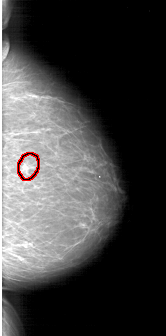

FILE: A_1403_1.RIGHT_MLO.OVERLAY

TOTAL_ABNORMALITIES 1

ABNORMALITY 1

LESION_TYPE MASS SHAPE IRREGULAR MARGINS SPICULATED

ASSESSMENT 5

SUBTLETY 5

PATHOLOGY MALIGNANT

TOTAL_OUTLINES 1

BOUNDARY